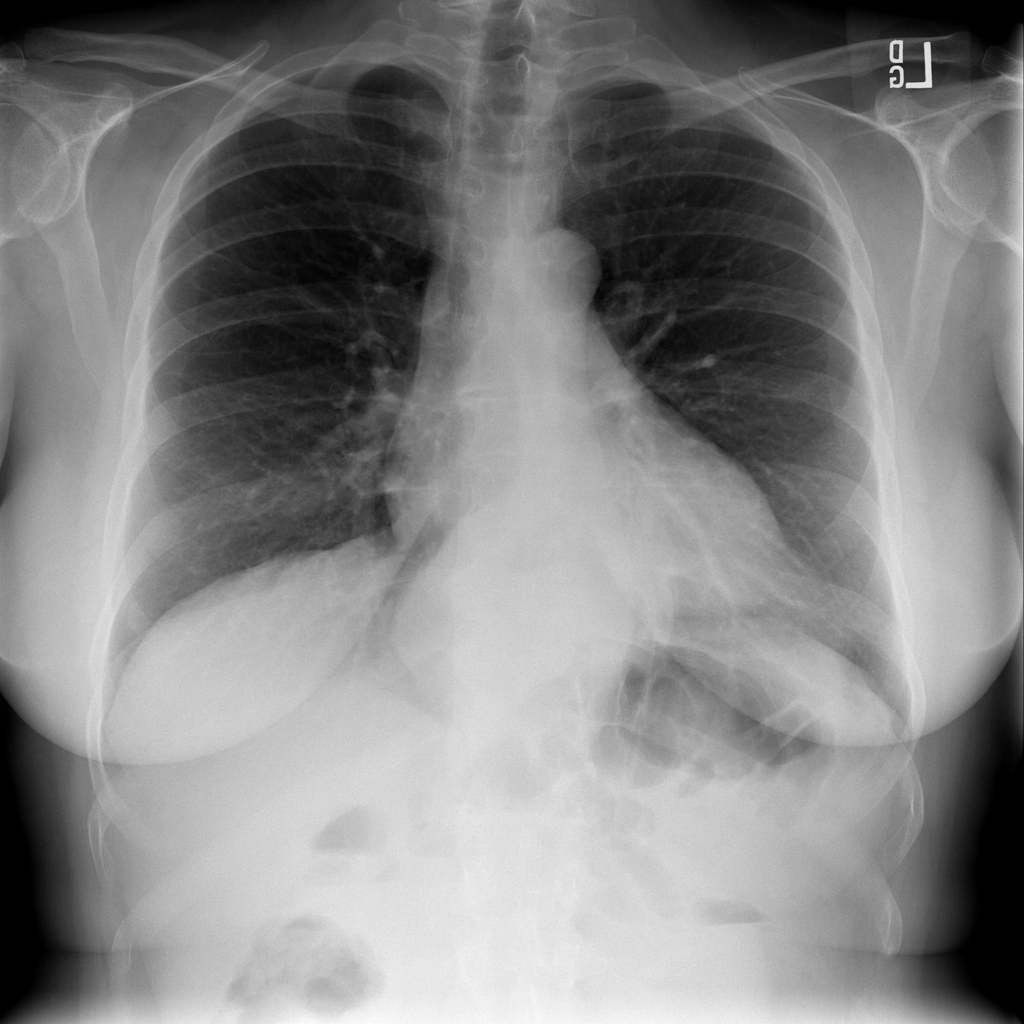

Showing up to 90 reference images for Hernia.

PAT-4F7E · IMG-000Hernia

PAT-4F7E · IMG-000

PA